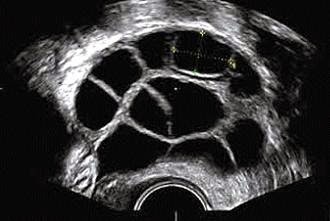

La reserva ovárica de una mujer puede estimarse mediante el análisis en sangre de ciertas hormonas. Un valor elevado de la hormona FSH (más de 10-12mUI/ml) entre el tercer y quinto día del ciclo menstrual indica una reserva ovárica reducida.

La punción folicular es el proceso quirúrgico mediante el cual se extraen los ovocitos de una mujer durante un tratamiento de Fecundación in Vitro (FIV). La mujer es estimulada previamente con hormonas con el fin de obtener el crecimiento simultaneo del máximo numero posible, de folículos por ovario. Una vez estos folículos alcanzan la medida optima se induce la ovulación mediante una inyección de ...